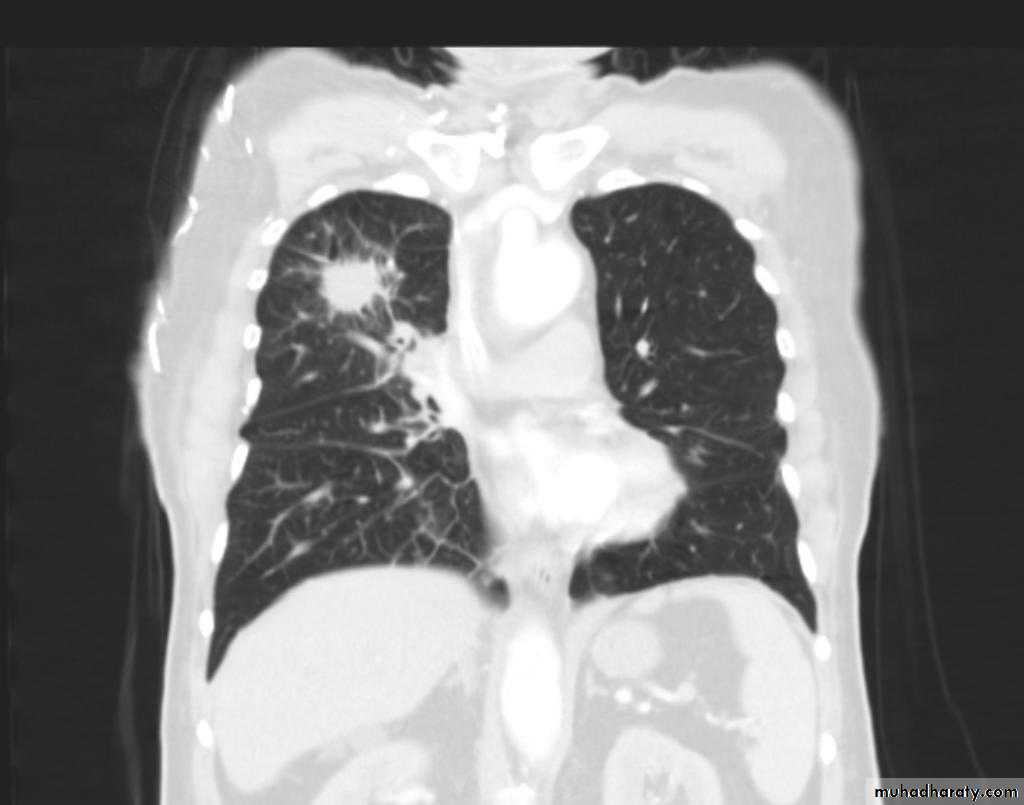

TB lung abscess

CT scan show cavity with air fluid level inside it in the upper lobe of the right lung.

Cavity with air fluid level inside in the uper lobe of the right lungAspergilloma